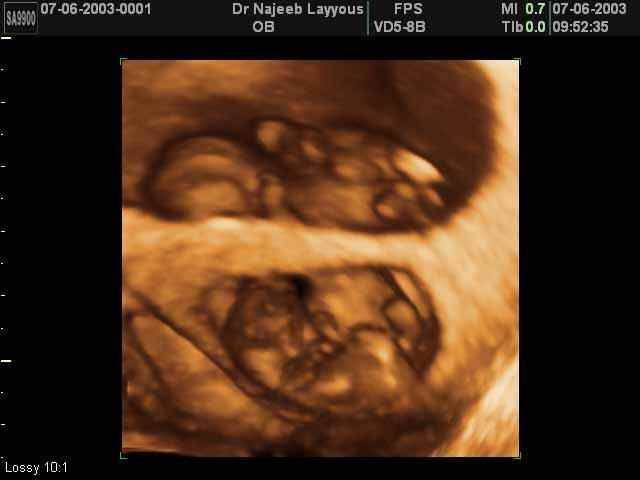

- 3D Photos échographie de grossesse multiple